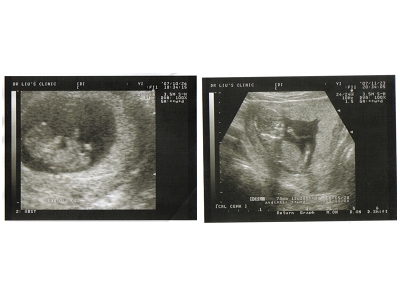

大家看的出來這是什麼嗎~~(其實在我沒懷孕之前~大家的超音波我實在是有看沒有懂啊~)~

所以為了方便大家了解~這團黑黑的到底是什麼~~我特別做了圖解~~

哎~虧這次小米同學腿還開大大的~可是什麼都不知道~~整個殘念~~

小米跟上次比較起來~

這次最不一樣的就是他的五官可以明顯的看出來了~

大家看的出來嗎~~~整個就像個外星寶寶一樣~~

這個月~小米又很努力的在長大~~

上次的他只有2.9公分~這個月的他已經有7公分左右了~~

左邊是上次產檢10週的樣子~~右邊是這次14週的樣子~

感覺就是長大了許多~`